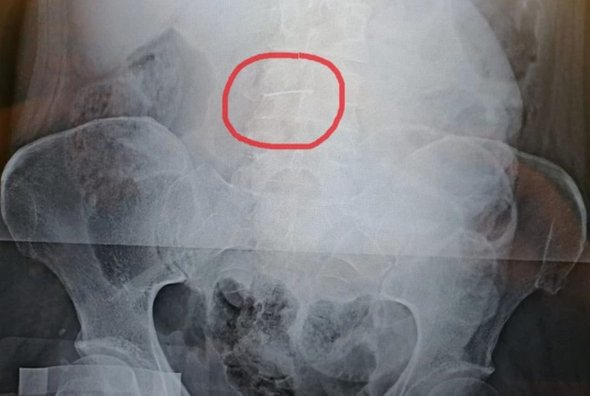

Длина швейной иглы составила 5 см. Однако медики долго не могли понять, каким образом игла могла попасть в брюшную полость. «Уже после операции пациентка рассказала, что приблизительно в 2004 году, работая на швейной фабрике, могла получить случайную травму, в результате которой игла попала в брюшную стенку, а затем видимо мигрировала в брюшную полость и застряла в сальнике», — рассказали медики.

фото: комитет здравоохранения Волгоградской области